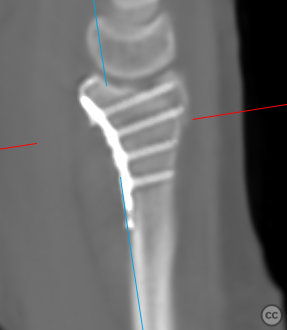

Oct 01 2024

By Dr Ed Oates

Distal Radius Fracture with Lunate Facet...

Schleswig Holstein, Germany

Radius - AO/OTA 2Rx